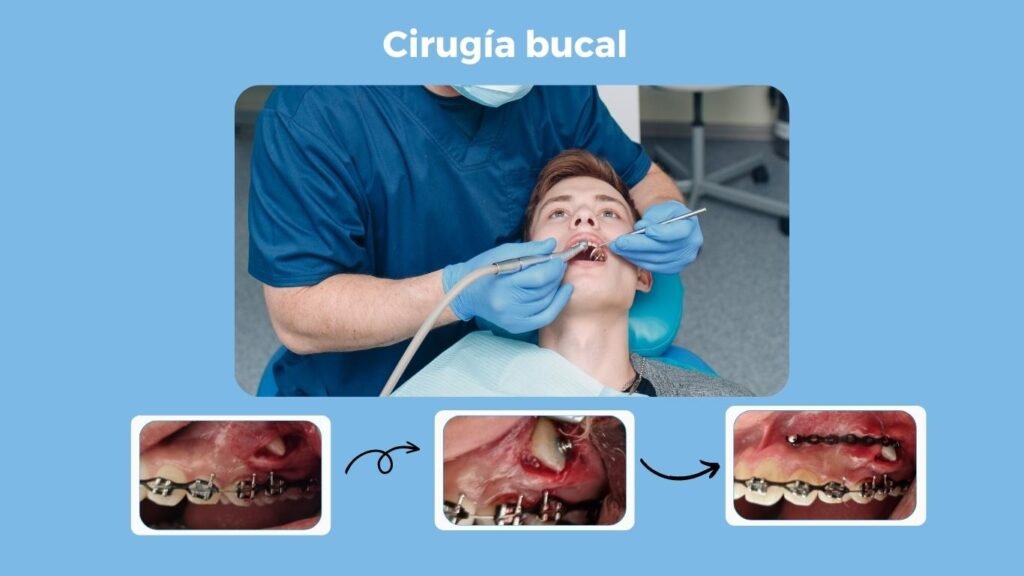

Cirugía bucal

Si tus “muelas del juicio” son un dolor de cabeza, de manera literal, te ofrecemos el tratamiento por elección, que es extraer tus muelas; ya sea para eliminar el dolor que estén ocasionando o para prevenir a futuro este tipo de malestares.

En el área de la cirugía bucal, también podemos tratar tus dientes que se encuentran “atrapados” en el hueso, ya sea para retirarlos por completo o para alinearlos por medio de un tratamiento de ortodoncia. No lo pienses más, y acude a nuestras instalaciones para realizar tu tratamiento.